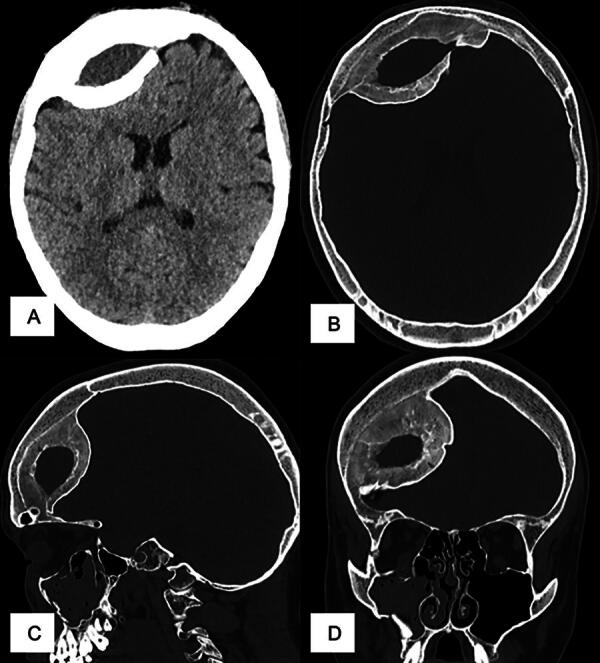

The presence of a calcified or ossified chronic cranial epidural hematoma (EDH) is rare and has been described in only a few case reports in the literature. Consequently, clear treatment strategies remain elusive and may entail conservative and surgical approaches. In this study, we performed a systematic review of reported cases to evaluate the clinical course and treatment options for these patients. A comprehensive systematic search of two databases was performed, and information on patient characteristics, symptomatology, and treatment was extracted from eligible articles. A total of 56 cases were included in our analyses. Forty patients were male, 16 were female, with an average age of 21.38 years at the time of diagnosis. Assumed etiology was previous trauma in 35 cases, previous cranial surgery in 17 patients, and birth trauma and epidural bleeding after the utilization of the Mayfield clamp in 1 case each. The origin remained unclear in two cases. The time between trauma or surgery and diagnostics ranged between one and a half weeks and 50 years, with a median of 4 years (SD 9.8 years). The symptoms were very heterogeneous, ranging from acute neurological deterioration to chronic symptoms. In 15 cases, patients were asymptomatic, and cranial imaging was performed as part of a new trauma or a screening for other disease. Forty-one patients received surgical treatment by craniotomy and hematoma evacuation, and 13 patients were treated conservatively. In two cases, the liquid hematoma portion was aspirated through a burr hole. The localization of calcified or ossified EDH was mainly supratentorial. Young male patients most commonly present with calcified or ossified EDH after trauma, according to the epidemiological trend of acute EDH. Clinical presentation varies from asymptomatic to severe neurological deficits and signs of increased intracranial pressure. There is no standardized treatment; decisions must be made on an individual basis.

Abstract Image